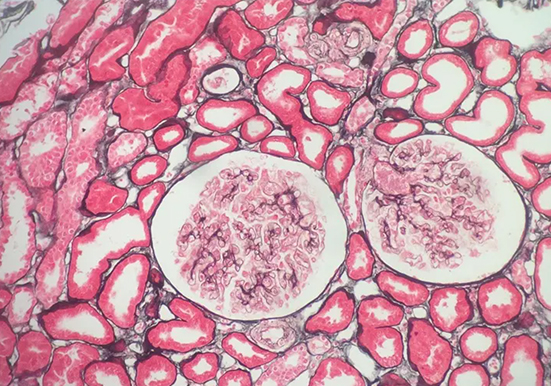

刚果红染色

刚果红染色是一种常用的生物染色方法,以下是关于它的详细介绍:

染料性质:刚果红是一种经典的酸性染料,化学式为 C32H22N6Na2O6S2,是一种棕红色粉末,能溶于水和乙醇。

染色原理:主要依赖于其与蛋白质及其他生物大分子的亲和性,通过静电吸引、氢键等作用力与样品中的不同组分发生相互作用,使样品呈现出特定的颜色。

组织切片准备:将组织样本用福尔马林固定,然后进行石蜡包埋,再切成薄片。

脱蜡与水化:将切片依次放入二甲苯 Ⅰ、二甲苯 Ⅱ 中各 15min 进行脱蜡,然后依次经过无水乙醇 Ⅰ、无水乙醇 Ⅱ 各 5min,90% 乙醇、80% 乙醇、70% 乙醇各 5min 进行水化。

染色:将切片放入刚果红工作液中染色 10min,然后用流水冲洗 1min。

分化:将切片放入碱性乙醇溶液中分化 1-3s,再用流水冲洗 1min。

复染:常用苏木精进行复染,将切片放入苏木精染液中染色 2min,然后用流水冲洗 1min。

脱水与透明:将切片依次放入 70% 乙醇、80% 乙醇、90% 乙醇、95% 乙醇、无水乙醇中各 5min 进行脱水,最后放入二甲苯中 5min 进行透明。

封片:用中性树胶将切片封片,以便于显微镜观察。